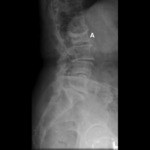

Ressonância nuclear magnética da estenose da coluna vertebral: a seta aponta para o canal vertebral com estenose moderada causada por facetas hipertróficas e ligamento amarelo

Cortesia do Dr K. Singh; usado com permissão